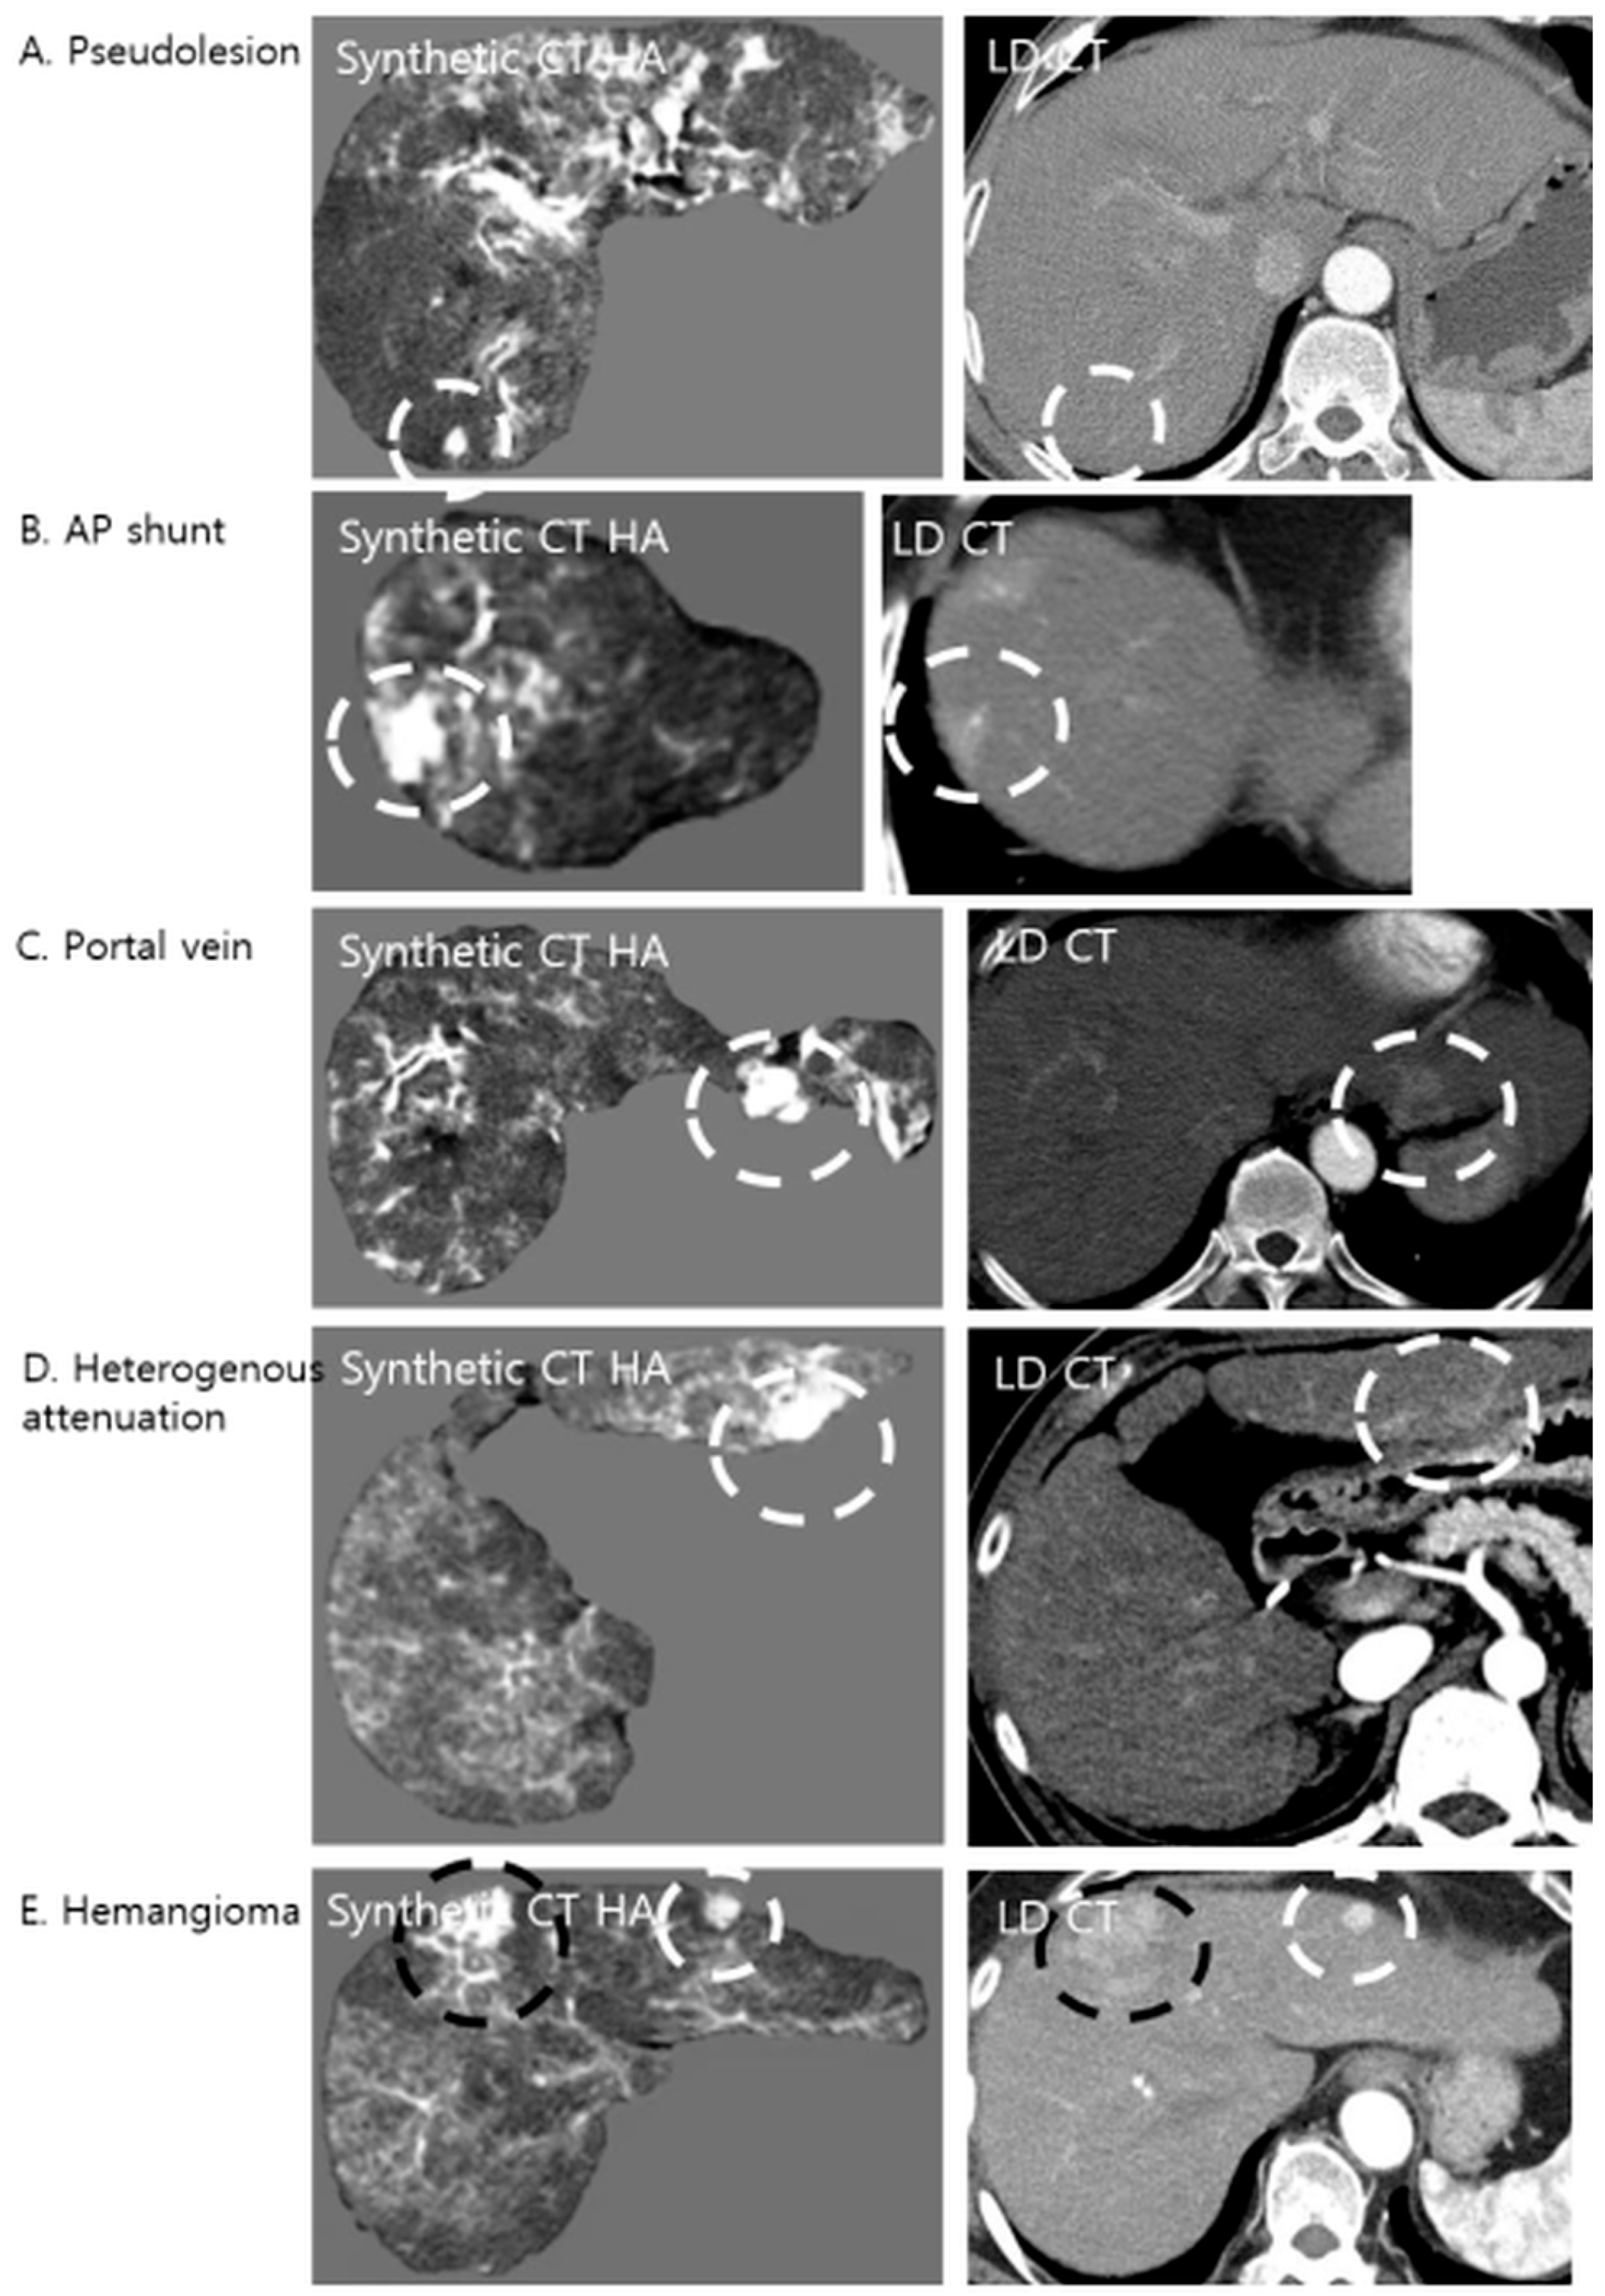

Retrospective analysis of the corresponding LDCT images revealed the primary cause of these false positives (Figure 4). The predominant etiology was an arterioportal (AP) shunt (n = 47), which accounted for the majority of cases. Since AP shunts exhibit early arterial enhancement, physiologically mimicking HCC, the model, which was trained to amplify hypervascular features, accentuated these regions, rendering them nodular in appearance. Other anatomical confounders included cross-sections of the hepatic vessels (n = 15), focal areas of heterogeneous liver parenchyma (n = 14), and flash-filling hemangiomas (n = 2), all of which presented high attenuation values that the algorithm interpreted as potential lesions.

Figure 4. Examples of false-positive lesions on Synthetic CTHA. The algorithm may enhance non-tumorous structures, mimicking hypervascular nodules. The white dashed circles indicate pseudolesions, while the black dashed circles indicate the confirmed hypervascular hepatocellular carcinoma (HCC) lesions. (A) A pseudolesion generated in the absence of any enhancing structure on LDCT. (B) An arterioportal (AP) shunt showing early enhancement is accentuated, appearing nodular. (C) A cross-section of a portal vein mimicking a nodule. (D) Focal heterogeneous liver attenuation amplified by the model. (E) A flash-filling hemangioma showing enhancement patterns similar to HCC on the synthetic image.